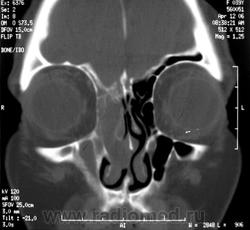

Затылочное экцефалоцеле.

Приложения: